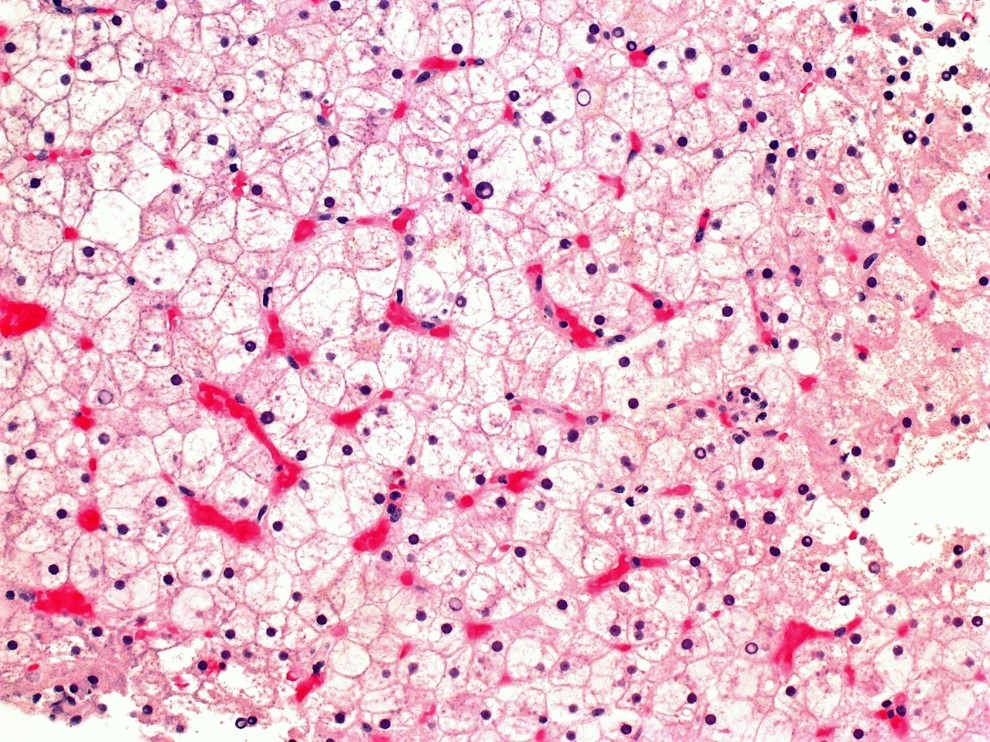

A 20-year-old man presented to the ER with symptoms of diabetic ketoacidosis. After stabilization, lab work revealed elevated liver enzymes. Liver biopsy was performed. What is his condition?

Answer: C.) Glycogenic hepatopathy